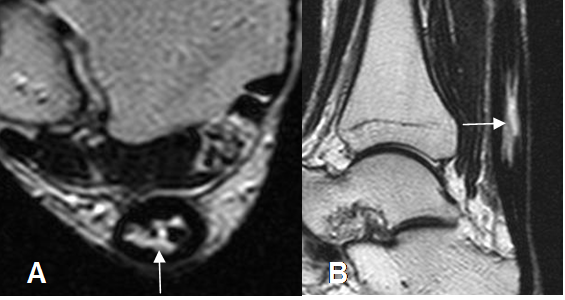

Fig 80. Tendinosis del aquiles.

A: RM axial en T2 y B: RM sagital en T2. Tendón engrosado, con borde anterior convexo e imagen hiperintensa intrasustancia por ruptura parcial o degeneración mucoide.